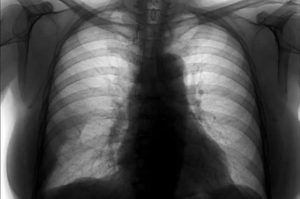

Диагностика начинается с выслушивания жалоб пациента, затем тщательный сбор анамнеза и проведение общего осмотра. В результате осмотра могут обнаружиться:

- При перкуссии – притупление перкуторного звука над очагом фиброза;

- При аускультации – ослабление дыхание, появление дыхательных шумов, бронхофония.

На основании полученных данных, врач назначает специальные методы обследования, как правило это инструментальные методики, так как лабораторные тесты малоинформативны. В общем анализе крови могут наблюдаться признаки анемии (полицитемия, ретикулоцитоз). В более поздних стадия могут наблюдаться признаки поражения многих органов и тканей в биохимическом анализе крови.